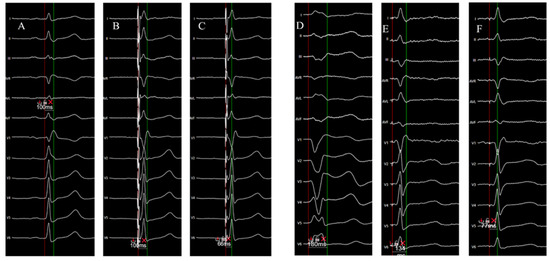

Left Bundle Branch Area Pacing in Cardiac Resynchronization Therapy: How Does It Compare to Biventricular Pacing in Terms of Electrocardiographic Parameters and Procedural Outcomes?

Background/Objectives: Biventricular pacing (BVP) to deliver cardiac resynchronization therapy (CRT) is a standard intervention for heart failure, yet suboptimal response remains common due to challenges in left ventricular (LV) lead placement. Left bundle branch area pacing (LBBAP) has emerged as a promising [...] Read more.

Background/Objectives: Biventricular pacing (BVP) to deliver cardiac resynchronization therapy (CRT) is a standard intervention for heart failure, yet suboptimal response remains common due to challenges in left ventricular (LV) lead placement. Left bundle branch area pacing (LBBAP) has emerged as a promising alternative, offering physiological activation via direct conduction system engagement. However, comparative data on electrocardiographic (ECG) and procedural outcomes between LBBAP-CRT and BVP-CRT are limited. Methods: This retrospective, single-center study compared LBBAP-CRT and BVP-CRT in 114 patients with left bundle branch block and LV ejection fraction ≤ 35%. LBBAP-CRT was performed using a Medtronic SelectSecure™ 3830 lead via a fixed-curve sheath Medtronic C315HIS, with successful capture confirmed by ECG criteria (Qr/qR in V1, LV activation time < 100 ms). BVP-CRT involved coronary sinus LV lead placement. Outcomes included QRS duration, pacing thresholds, complications, and procedural metrics. Statistical analysis employed logistic regression to identify predictors of optimal pacing thresholds (≤1.0 V at 0.5 ms). Results: LBBAP-CRT yielded greater degree of QRS narrowing than BVP-CRT (136.7 ± 13.5 ms vs. 147.2 ± 14.6 ms, p < 0.001) and lower pacing thresholds (p < 0.05). Complications occurred in 18.1% of BVP-CRT patients (phrenic nerve stimulation, lead dislocation) versus none in LBBAP-CRT (p = 0.011). According to the multivariable analysis LBBAP-CRT was associated with an optimal thresholds (p = 0.007), alongside lower E/e′ ratio and lead impedance. Conclusions: LBBAP-CRT was associated with superior electrical resynchronization, fewer complications, and better pacing thresholds compared to BVP, suggesting its potential as a preferred CRT strategy. Larger randomized trials are needed to validate long-term outcomes. Full article